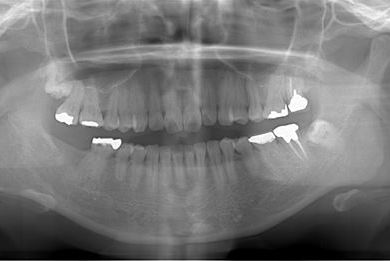

インプラントの症例写真 IMPLANT

インプラント治療+セラミック治療+歯肉歯槽骨整形

| 性別/年齢 | 女性 / 38歳 | ||||||||||||||||||||||||||||||||

| 主訴 | 右下奥の欠損のため、インプラントを希望。また、左に物が挟まりやすいための治療も希望。 | ||||||||||||||||||||||||||||||||

| 治療内容 | インプラント1本、ジルコニアフレームオールセラミッククラウン2本(ジルコニアセラミック用土台1本)、歯肉歯槽骨整形 | ||||||||||||||||||||||||||||||||

| 総治療費 | 713,580円 | ||||||||||||||||||||||||||||||||

| 治療期間 | 10ヶ月 |